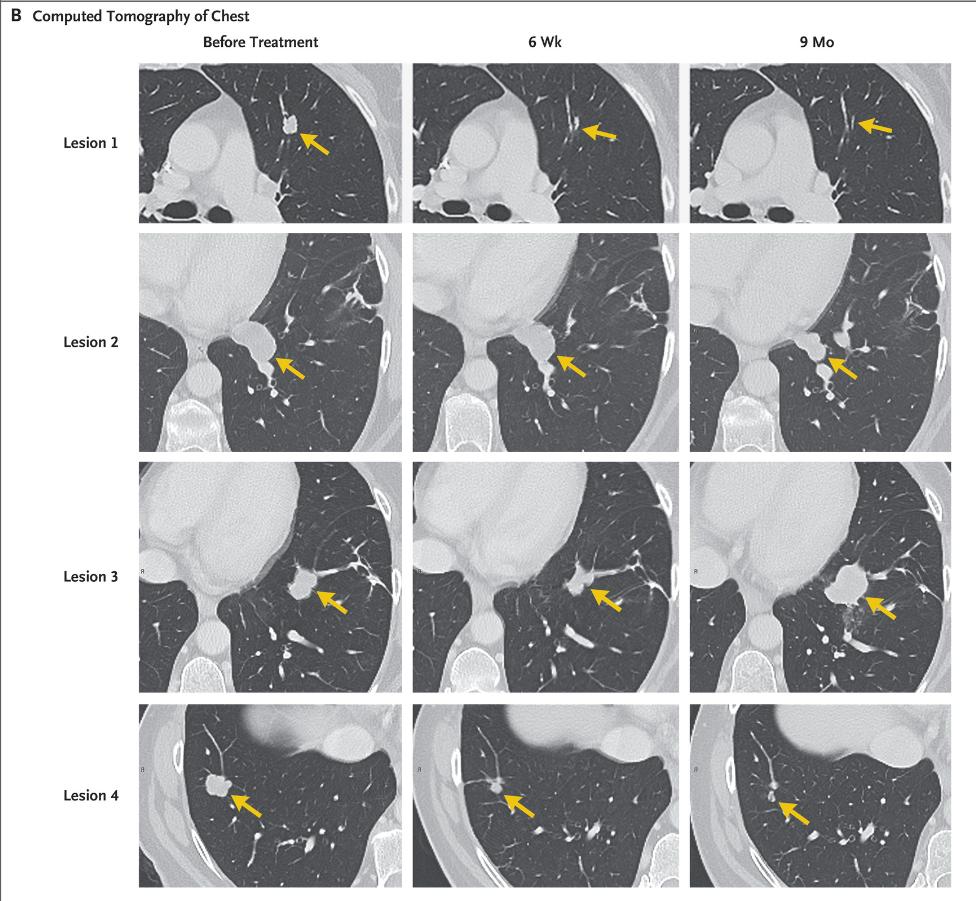

2016年顶级医学杂志《新英格兰杂志》上报道的一款新型免疫疗法震惊整个肿瘤界,因为这款疗法令致命的晚期KRAS突变的结直肠癌患者肺部7个转移病灶全部消退。

2013年,Celine Ryan不幸患上结肠癌,在接受放疗与化疗之后癌症还是不断复发,并且癌细胞由结肠转移到肺部,长出了7个肿瘤。在走投无路的情况下,Ryan参与到了美国国立癌症研究所的一项TIL临床试验中。

研究人员发现Ryan的肿瘤组织中存在大量KRAS G12D突变。通过进一步筛选并提取能够特异性识别突变KRAS G12D的CD8+T细胞,在体外进行扩增培养。最后, 研究人员将1480亿个体外培养好的肿瘤浸润淋巴细胞注射进了Ryan体内,让这些肿瘤浸润淋巴细胞去对抗癌细胞。

在随后的9个月中,Ryan肺部的7个肿瘤中,有6个明显缩小,并最终消失。 最后一个对治疗没有反应的肿瘤则通过手术被医生切除。如今,她的体内已经检测不到任何癌细胞了。

免疫疗法抗肿瘤效果图,央视新闻报道免疫细胞治疗癌症

△肿瘤转移病灶几乎消失殆尽